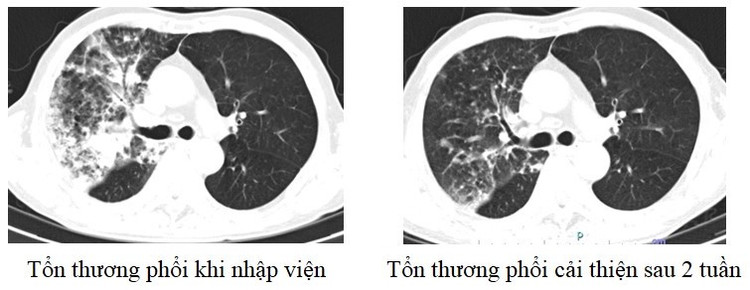

Tương tự, người bệnh nam 75 tuổi ở Hạ Hòa, Phú Thọ có tiền sử tăng huyết áp vào viện vì ho khạc đờm, khó thở. Chụp phim cho thấy tổn thương viêm diện rộng phổi trái. Do người bệnh cao tuổi, lại có nhiều bệnh nền nên thời gian điều trị kéo dài. Sau 2 tuần, sức khỏe người bệnh mới ổn định và được ra viện.

| Hình ảnh phổi của người bệnh 75 tuổi trước và sau khi điều trị |